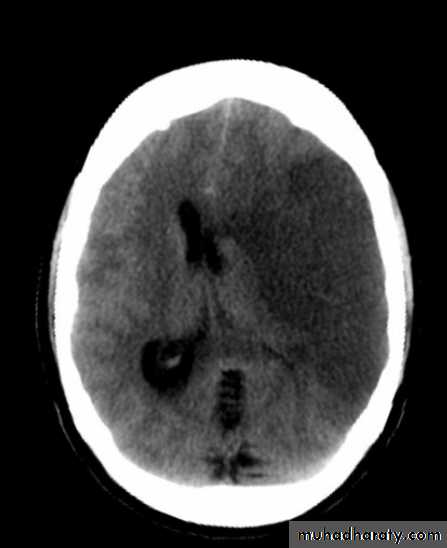

ACUTE INFARCTION

* wedge shape hypo density area.* Shifting of the midline & frontal horn

Chronic infarction

Hypo density area(pore encephalic cyst)Dilated ventricle